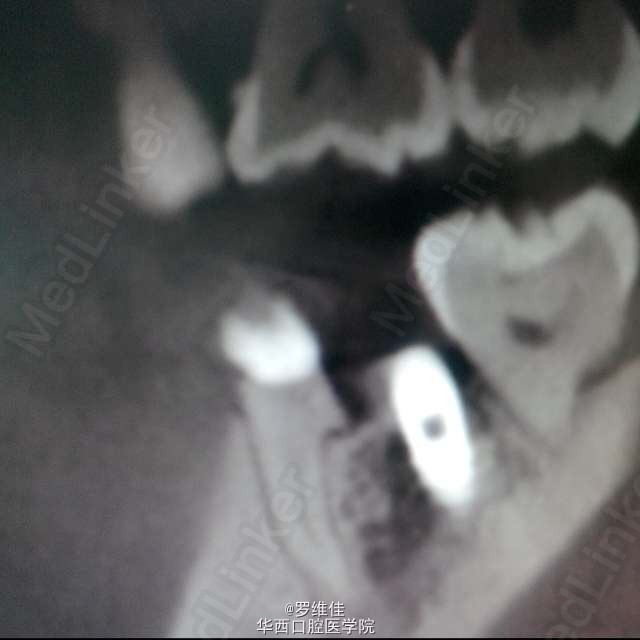

患者,女,29岁,D区的第一恒磨牙(分为近中根和远中根)远中根根管治疗后失败,根尖周有暗影,炎症反应,而近中根完好。原定计划方案:拔除第一恒磨牙,原位种植修复。但患者极其强烈要求保住近中根,只拔除远中根。根据患者极其特殊的要求改变治疗计划为:分根,拔除远中根,远中根原位植入种植体一枚,近中根备牙后进行烤瓷冠修复,目前种植体已植入,冠正在制作中